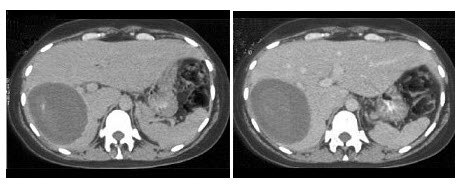

D.肾出血后

25、单项选择题

如图所示,根据这两个时相分析,最可能的诊断是()

A.肾淋巴瘤